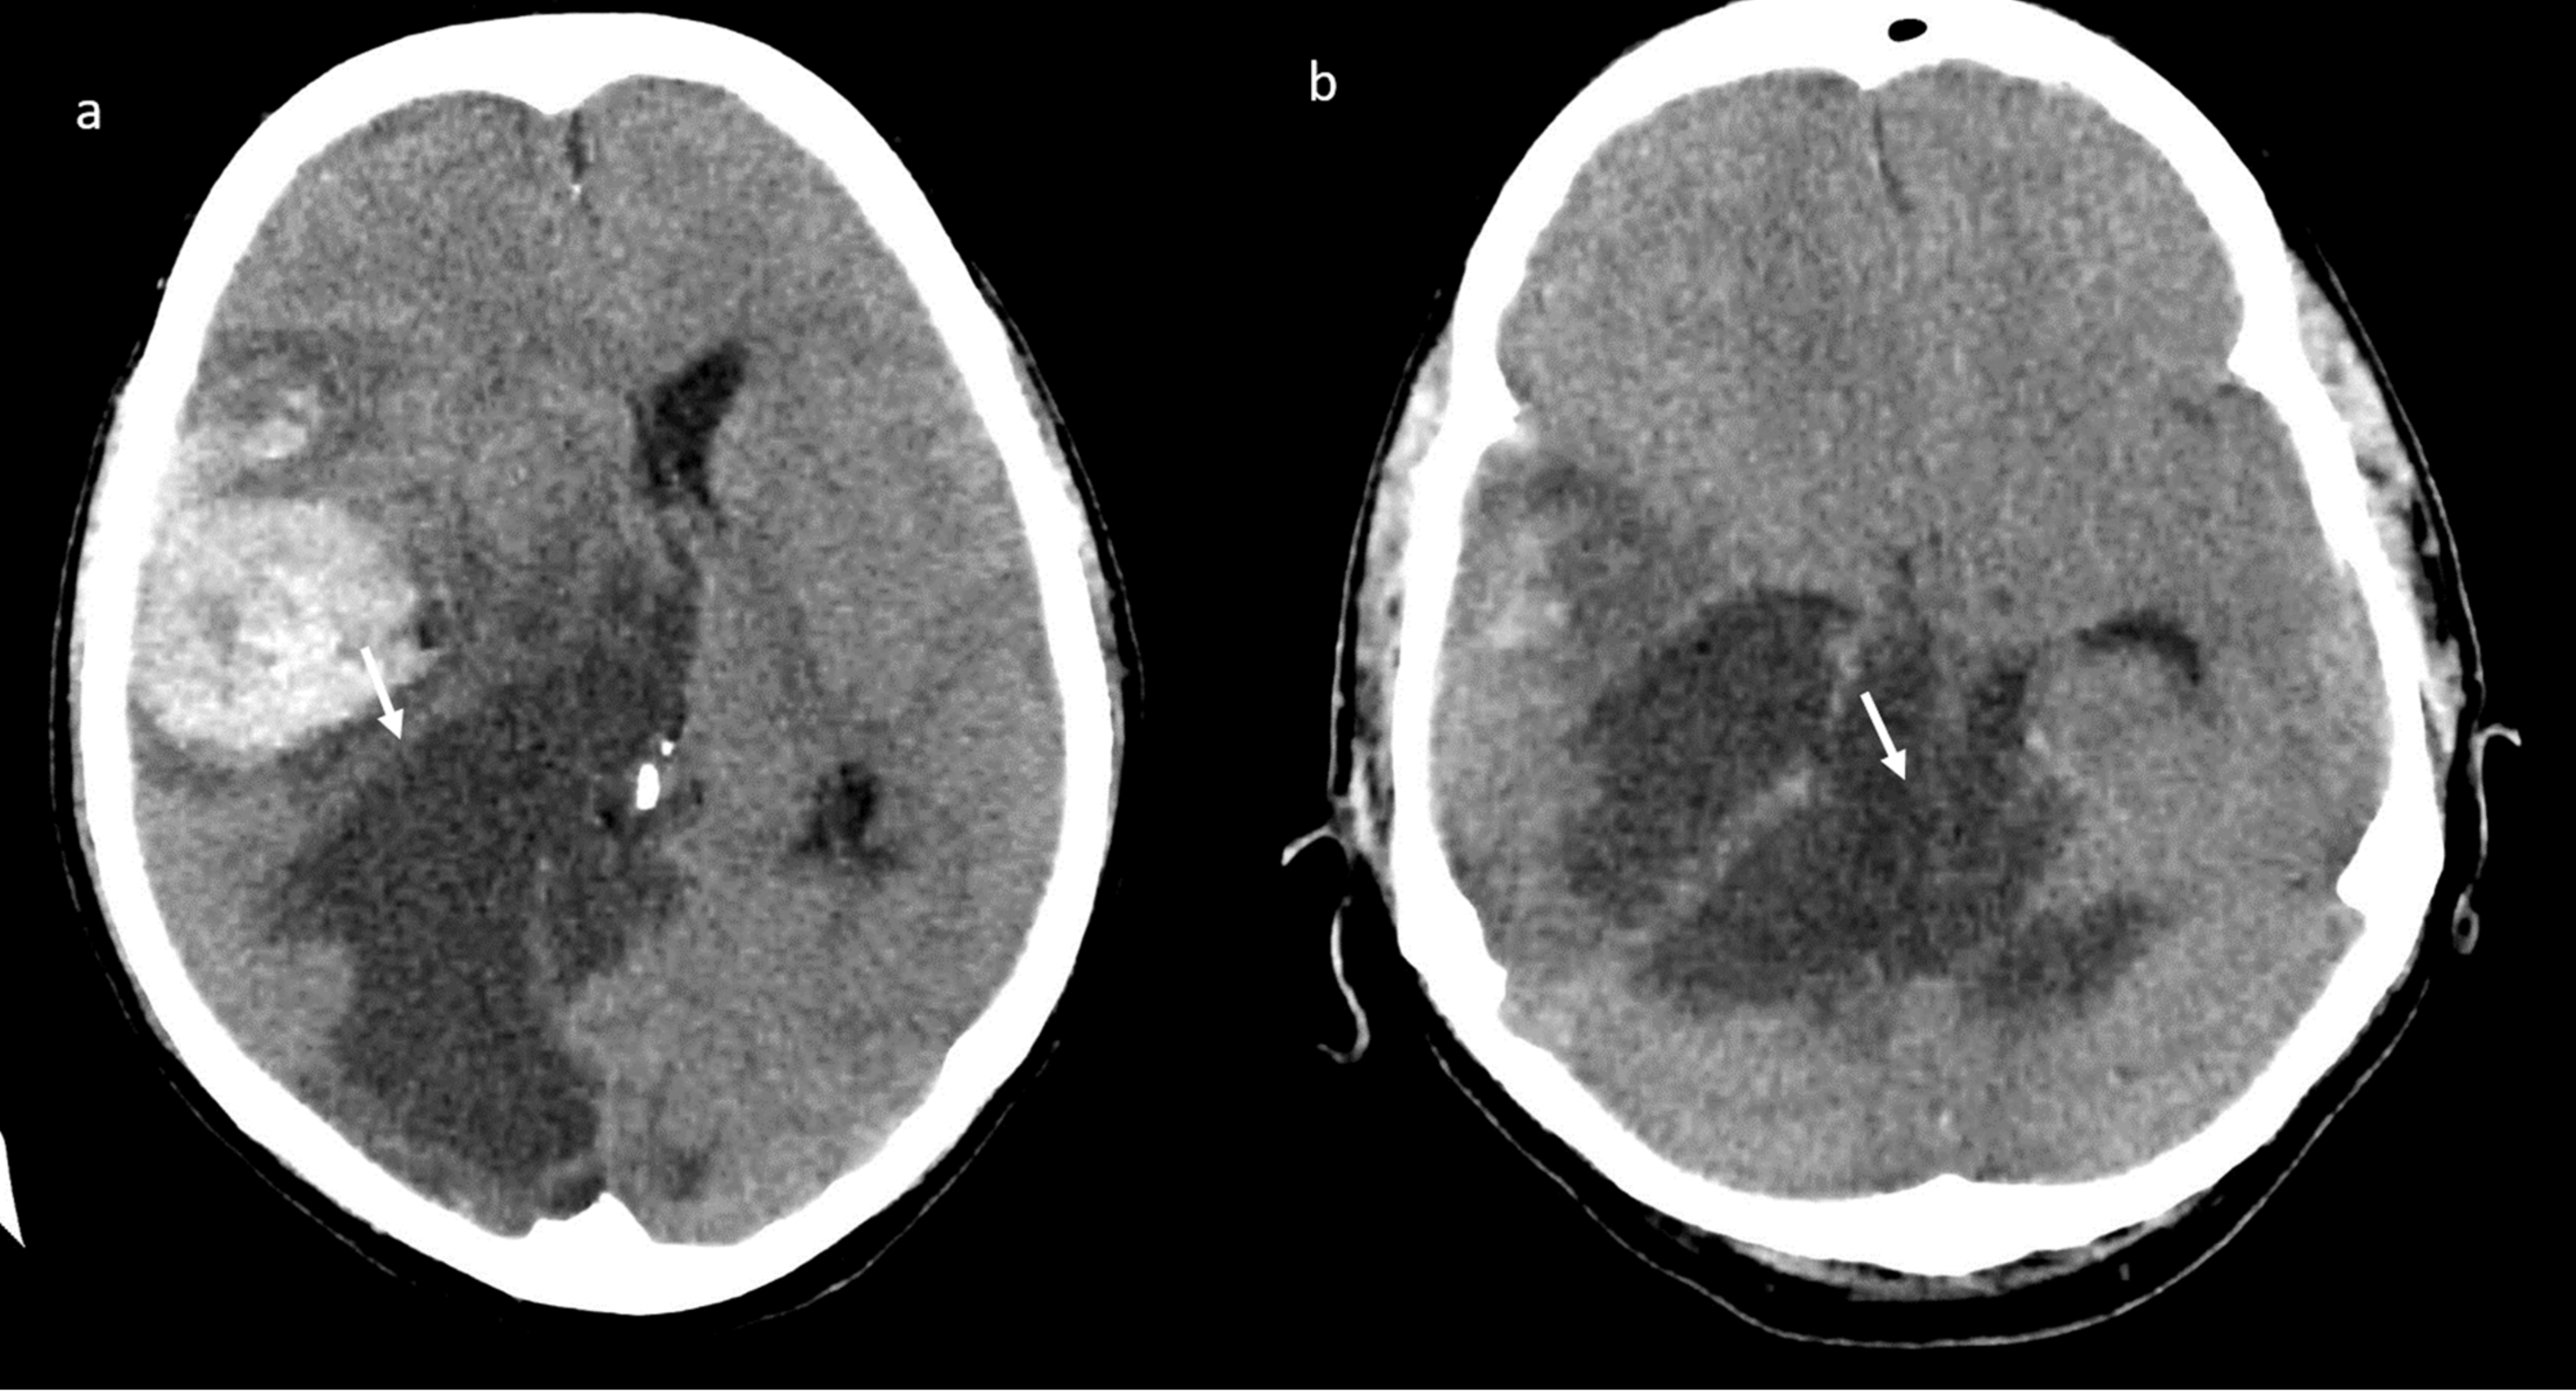

A brain computed tomography (CT) scan showed multiple subacute intra-axial hemorrhages in atypical locations, including the right frontal and the temporal lobes (Figure 1), with ipsilateral hemorrhagic subarachnoid suffusion, raising the suspicion of Labbè/superior longitudinal sinus thrombosis, even if brain angio-CT demonstrated only a non-occlusive thrombosis of the vein of Galen (Figure 2a), but also a floating thrombus within the aortic arch (Figure 2b).

Figure 1.

Brain computed tomography (CT) scan: presence of multiple subacute intra-axial hemorrhages in atypical locations (a,b).